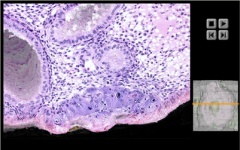

Carnegie Stage 5a-1 Movies

Surface View of Implantation Site

Trophoblast and Embryo